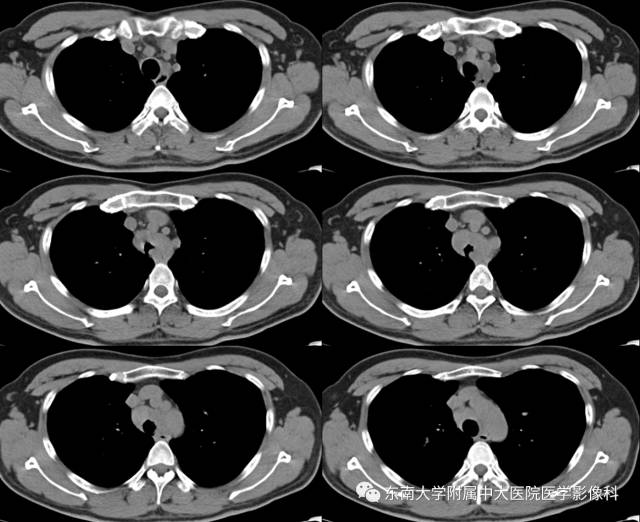

病例2

病史

女,65岁,因“气喘、气促半年余”入院。

CT

增强